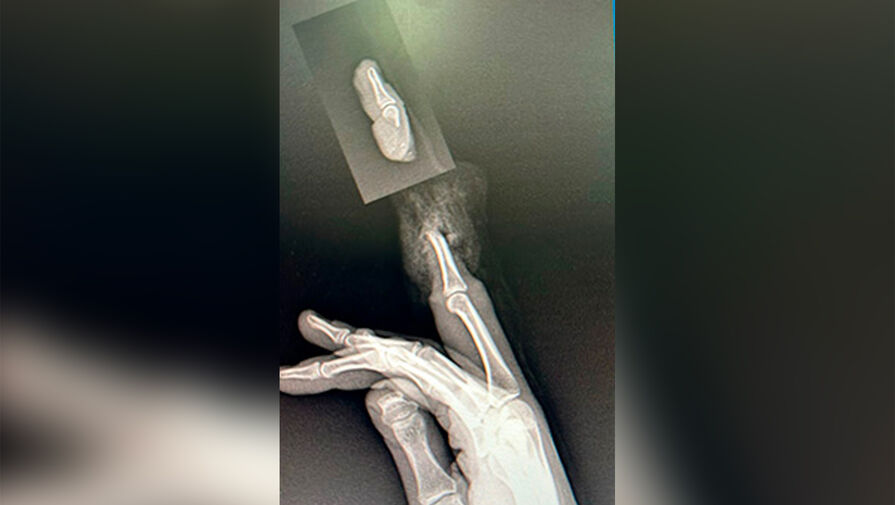

В Москве двум школьницам оторвало пальцы из-за колец. В Москве двум школьницам 12 и 14 лет пришили оторванные из-за колец пальцы. Информация об этом появилась на сайте детской городской клинической больницы имени Н.Ф. Филатова. Обе школьницы попали в детскую больницу почти одновременно. ...